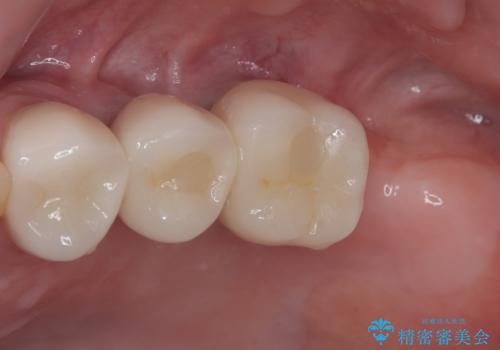

右下の銀歯も気になるとのことで、インプラント治療と並行してオールセラミックによるブリッジ補綴治療も行うこととしました。

地元に戻られる前に無事に治療を終えることができました。

今後は東京出張のタイミングでメインテナンスに通院していただきながら、インプラントの状態をチェックしていくことになります。